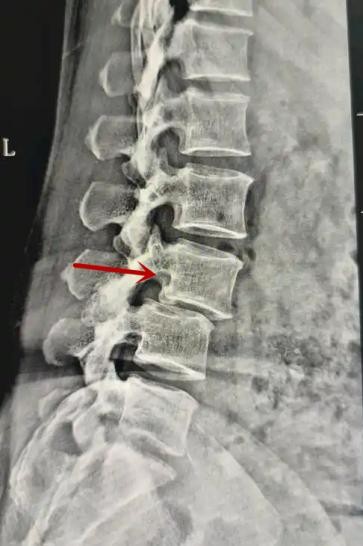

利器一:X线/DR

腰椎X线片作为最基础的影像检查手段,利于X线穿透人体组织后成像,以其快捷、直观、价格低廉的特点,X线检查主要包括腰椎正侧位、双斜位以及过伸过屈位。主要用于观察腰椎骨骼的情况,如椎体是否有骨折、骨质增生程度、生理曲度的变化、椎体移位的情况等。然而,X线检查也有它的局限性,无法判断是骨折的新旧,对于椎体内部结构和周围肌肉韧带组织(如脊髓神经、椎间盘、韧带等)的显示不佳,另外X线作为有辐射检查,孕妇及婴幼儿谨慎选择。

箭头提示腰1椎骨折

箭头提示腰3椎体滑脱